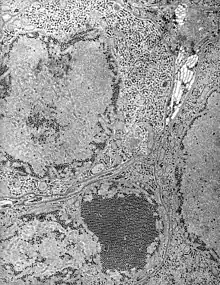

| Electron micrograph of Saint Louis encephalitis virus seen in a mosquito salivary gland | |